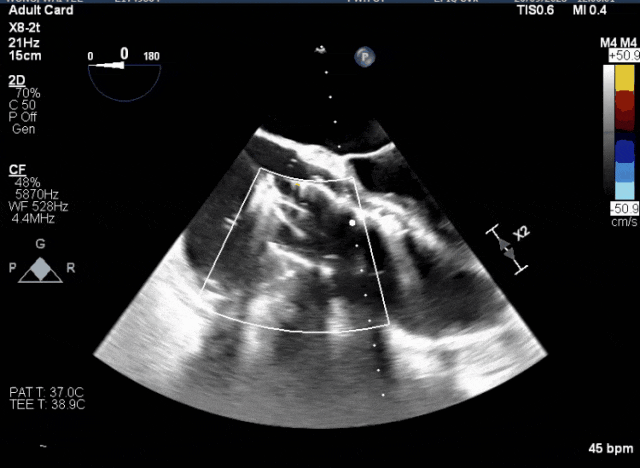

術(shù)中TEE成像困難,偽影干擾